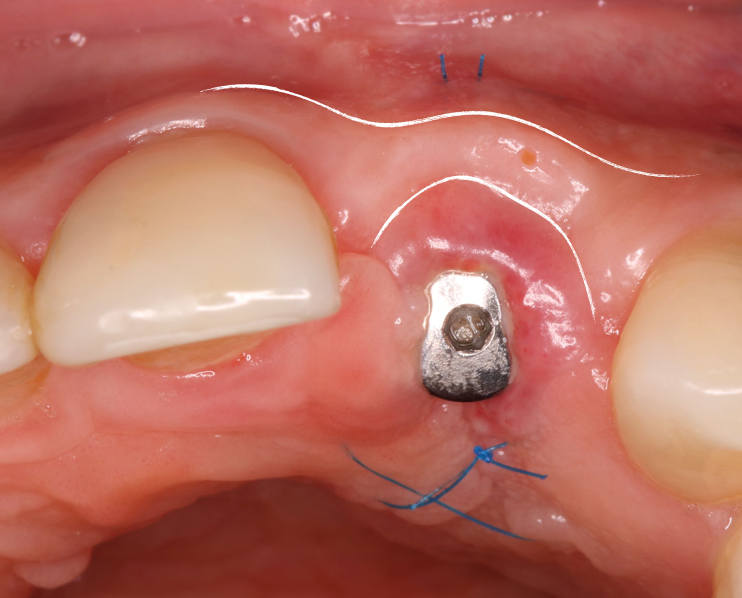

Utilizamos inicialmente um pilar de titânio anti-rotacional (AR) provisório para a captura do dente que estava na contenção estética removível. Assim, delimitamos todos os contornos e subcontornos das áreas críticas e subcríticas favorecendo a migração coronal da gengiva, resultando em uma melhor condição estética na posição da margem cervical do tecido mole (Frizzera, 2018). Fig.6A/B/C

Ao instalar o provisório, ainda pudemos melhorar a arquitetura do tecido em relação aos tecidos adjacentes utilizando um método clínico que é a técnica de compressão dinâmica, o objetivo desta técnica é estabelecer um perfil de emergência adequado, nivelar o contorno da margem gengival, zênite, largura da papila e a forma triangular do perfil e estabelecer um ponto de contato (Wittneben, 2013). Fig.7A/B/C